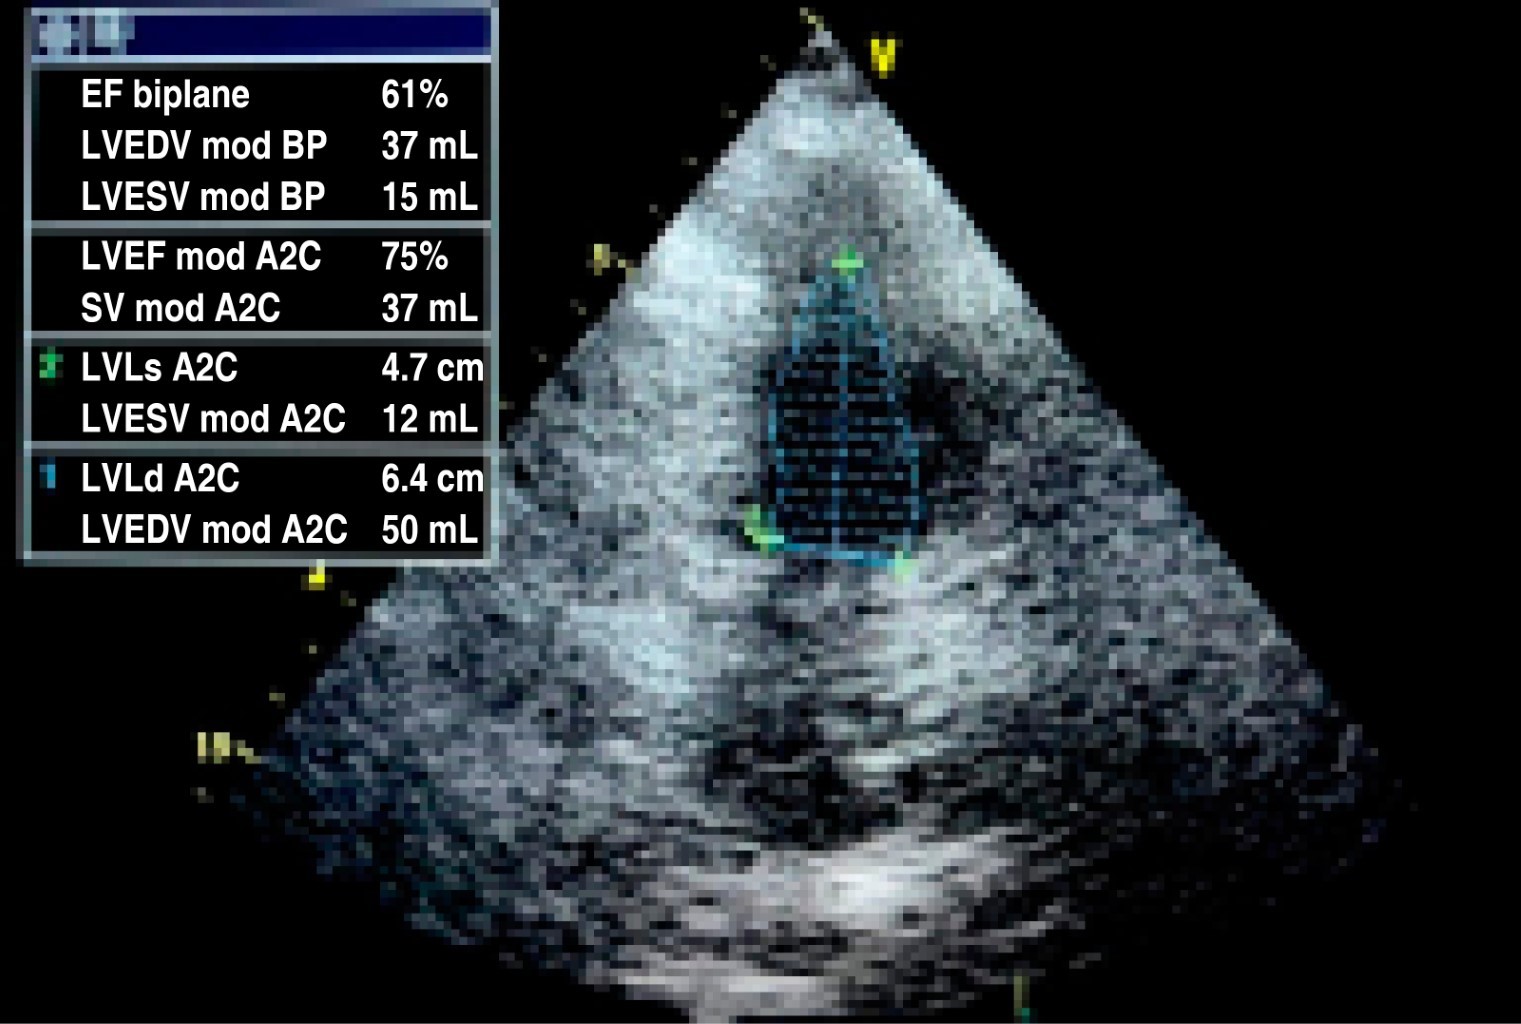

Figura 1